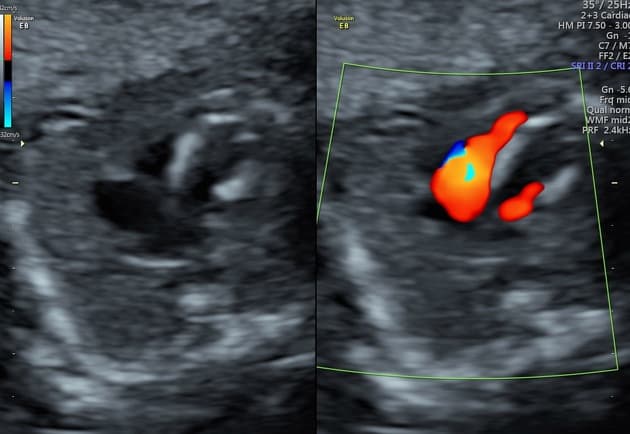

Còn ống động mạch

Không thấy tổn thương động mạch chủ do chấn thương hoặc máu tụ trung thất. Ghi nhận thấy ống động mạch còn thông (patent ductus arteriosus).

- Không tổn thương động mạch chủ do chấn thương. Ống động mạch còn thông có đường kính nhỏ, không có dấu hiệu tăng áp động mạch phổi hoặc phì đại thất phải (RV hypertrophy). Gợi ý hội chẩn với chuyên khoa Tim mạch (Cardiology review suggested).

Ống động mạch (ductus arteriosus) là một mạch máu nối động mạch chủ xuống gần đoạn đầu với phần trần của thân động mạch phổi gần nơi xuất phát của động mạch phổi trái. Bình thường, ống này tự đóng trong vòng 24–48 giờ sau sinh do tăng áp lực oxy và giảm nồng độ prostaglandin. Việc không đóng lại sẽ dẫn đến tình trạng ống động mạch còn thông (patent ductus arteriosus – PDA).

Trong bối cảnh chấn thương, việc phân biệt giữa PDA và tổn thương động mạch chủ do chấn thương là rất quan trọng. Trong trường hợp này, vị trí giải phẫu, không có bất thường thành mạch, cùng với việc không có máu tụ trung thất hoặc các tổn thương ngực đáng kể khác giúp khẳng định chẩn đoán PDA.

Ống động mạch còn thông (Patent ductus arteriosus)